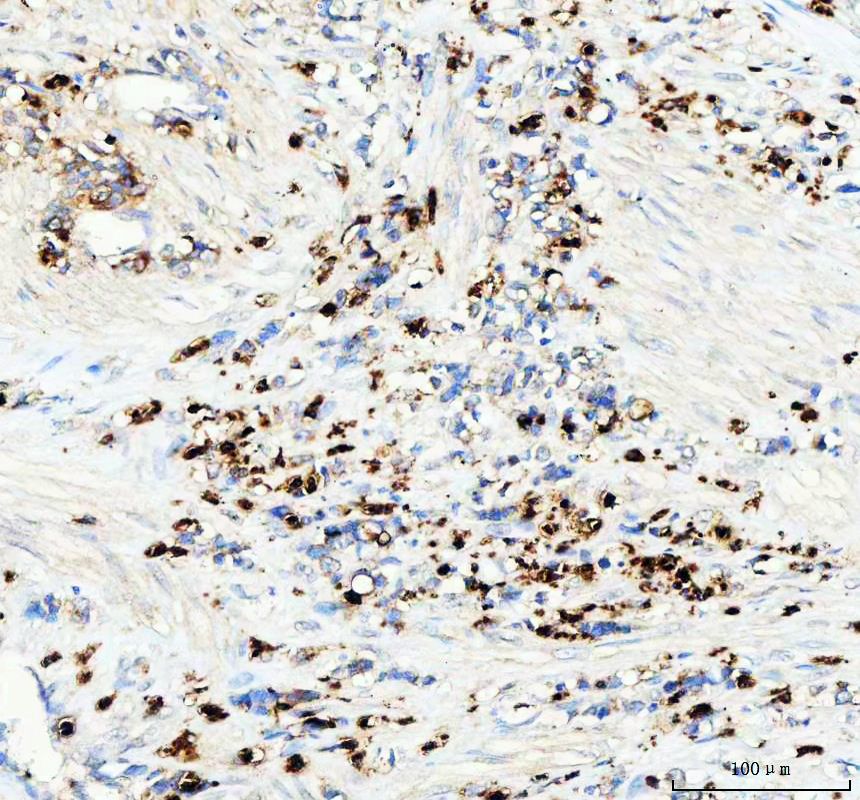

IHC analysis of Lysozyme/LYZ using anti-Lysozyme/LYZ antibody (BA0092) .

Lysozyme/LYZ was detected in a paraffin-embedded section of human gastric cancer tissue. The tissue section was incubated with rabbit anti-Lysozyme/LYZ Antibody (BA0092) at a dilution of 1:200 and developed using HRP Conjugated Rabbit IgG Super Vision Assay Kit (Catalog # SV0002) with DAB (Catalog # AR1027) as the chromogen.